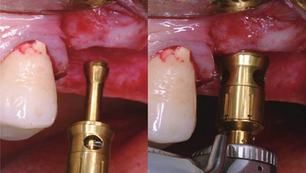

Ridge split procedure with ridge wider and simultaneous implant placement of IS III active fixtures

Situation A 58-year-old female patient had lost teeth 46 and 47 and was referred to the clinic for treatment. As extremely narrow ridge...